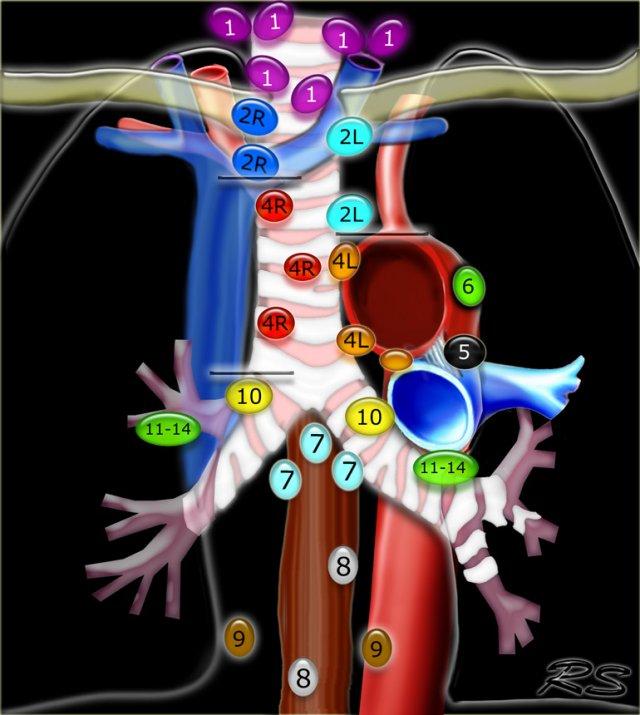

Bản đồ hạch lympho trung thất

Bản đồ hạch bạch huyết IASLC 2009

Phân loại hạch bạch huyết vùng trong phân giai đoạn ung thư phổi, được điều chỉnh từ sơ đồ phân vùng của Hội Lồng ngực Hoa Kỳ

1.Hạch cổ thấp, thượng đòn và hõm ức

Từ bờ dưới sụn nhẫn đến xương đòn và bờ trên của cán ức.

Đường giữa khí quản là ranh giới phân chia giữa nhóm 1R và 1L.

Hạch Trung thất Trên nhóm 2-4

2R.Cạnh khí quản trên

Hạch nhóm 2R trải dài đến bờ bên trái của khí quản.

Từ bờ trên của cán ức đến điểm giao nhau giữa bờ dưới tĩnh mạch vô danh (tĩnh mạch tay đầu trái) với khí quản.

2L.Cạnh khí quản trên

Từ bờ trên của cán ức đến bờ trên của quai động mạch chủ.

Hạch nhóm 2L nằm ở phía trái của bờ bên trái khí quản.

3A.Trước mạch máu

Các hạch này không tiếp giáp với khí quản như các hạch ở nhóm 2, mà nằm ở phía trước các mạch máu.

3P.Trước cột sống

Các hạch không tiếp giáp với khí quản như các hạch ở nhóm 2, mà nằm sau thực quản, tức là ở vị trí trước cột sống.

4R.Cạnh khí quản dưới

Từ điểm giao nhau giữa bờ dưới tĩnh mạch vô danh (tĩnh mạch tay đầu trái) với khí quản đến bờ dưới tĩnh mạch đơn.

Hạch nhóm 4R trải dài từ bờ bên phải đến bờ bên trái của khí quản.

4L.Cạnh khí quản dưới

Từ bờ trên của quai động mạch chủ đến bờ trên của động mạch phổi trái.

Hạch động mạch chủ nhóm 5-6

5. Dưới động mạch chủ

Các hạch này nằm trong cửa sổ phế động mạch (AP window), ở phía ngoài dây chằng động mạch.

Các hạch này không nằm giữa động mạch chủ và thân động mạch phổi mà nằm ở phía ngoài các mạch máu này.

6. Cạnh động mạch chủ

Đây là các hạch của động mạch chủ lên hoặc hạch cơ hoành, nằm ở phía trước và bên của động mạch chủ lên và quai động mạch chủ.

Hạch Trung thất Dưới nhóm 7-9

7.Dưới carina

8. Cạnh thực quản

Các hạch nằm dưới carina.

9. Dây chằng phổi

Các hạch nằm trong dây chằng phổi.

Hạch rốn phổi, thùy phổi và (phân) phân thùy nhóm 10-14

Tất cả các hạch này đều thuộc nhóm N1.

10. Hạch rốn phổi

Bao gồm các hạch tiếp giáp với phế quản gốc và các mạch máu rốn phổi.

Bên phải, trải dài từ bờ dưới tĩnh mạch đơn đến vùng gian thùy.

Bên trái, từ bờ trên động mạch phổi đến vùng gian thùy.